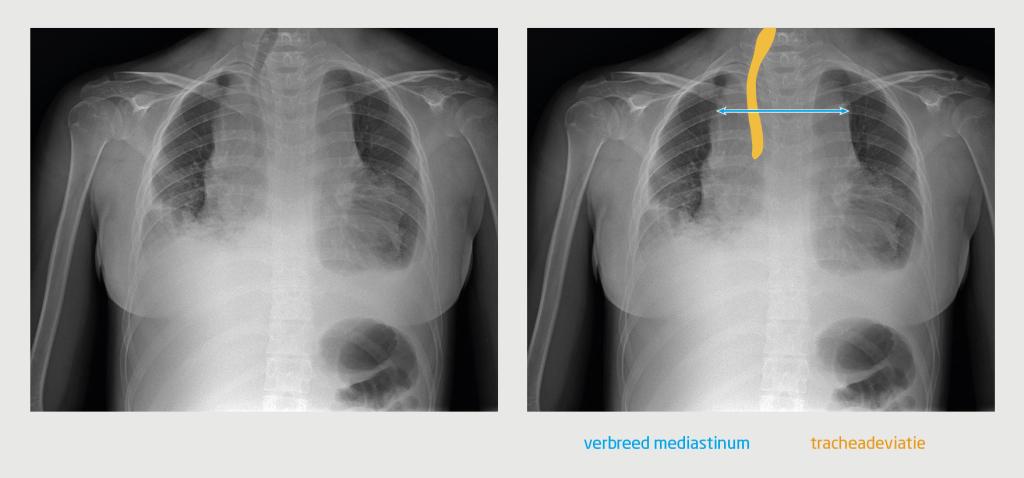

Aldaar werd een benauwd meisje gezien die in korte zinnen sprak. Er was sprake van neusvleugelen, orthopneu en oedeemvorming in het gelaat. De halsvaten waren gestuwd. Bij lichamelijk onderzoek palpeerde de anios kindergeneeskunde fors vergrote cervicale en supraclaviculaire lymfeklieren. Bij auscultatie van de longen hoorde zij bronchiaal en rechts basaal ook verminderd ademgeruis. De lever was 3 cm onder de ribbenboog palpabel. Omdat de zuurstofsaturatie daalde naar 93%, kreeg patiënte zuurstof toegediend. De röntgenfoto van de thorax toonde een fors verbreed mediastinum, waarschijnlijk veroorzaakt door een lymfadenopathie. De trachea was naar rechts verplaatst en beiderzijds was pleuravocht zichtbaar (figuur 1).

Figuur 1

Figuur 1 |

Anterieur-posterieure röntgenopname van de thorax van een 16-jarige meisje in zittende houding. De opname toont een verbreed mediastinum, een naar rechts verplaatste trachea en beiderzijds pleuravocht.